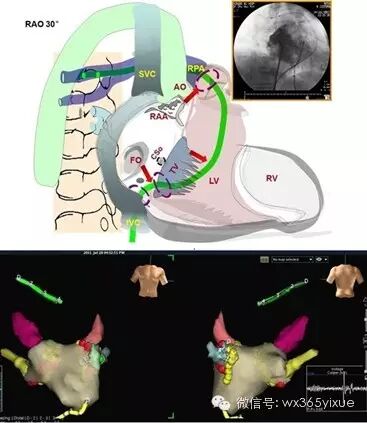

4.近“零射线”下放置导管:经外周血管穿刺放置导管时,X线透视为常规步骤。由于三维标测系统能够实时显示导管在腔内的形状,结合腔内电图的变化,无射线或近乎零射线下放置导管已成为可能(图3-1),对于儿童、孕妇等特殊人群尤其适用16,17。

图 3-1 应用EnSite™三位标测系统实现近乎”零射线“下导管到位。将模型的透明度设置为最高,持续建模,导管根据”点云“及腔内电图确定所在位置,完成到位上下腔静脉、右心房及跨过三尖瓣环进入右心室等操作。